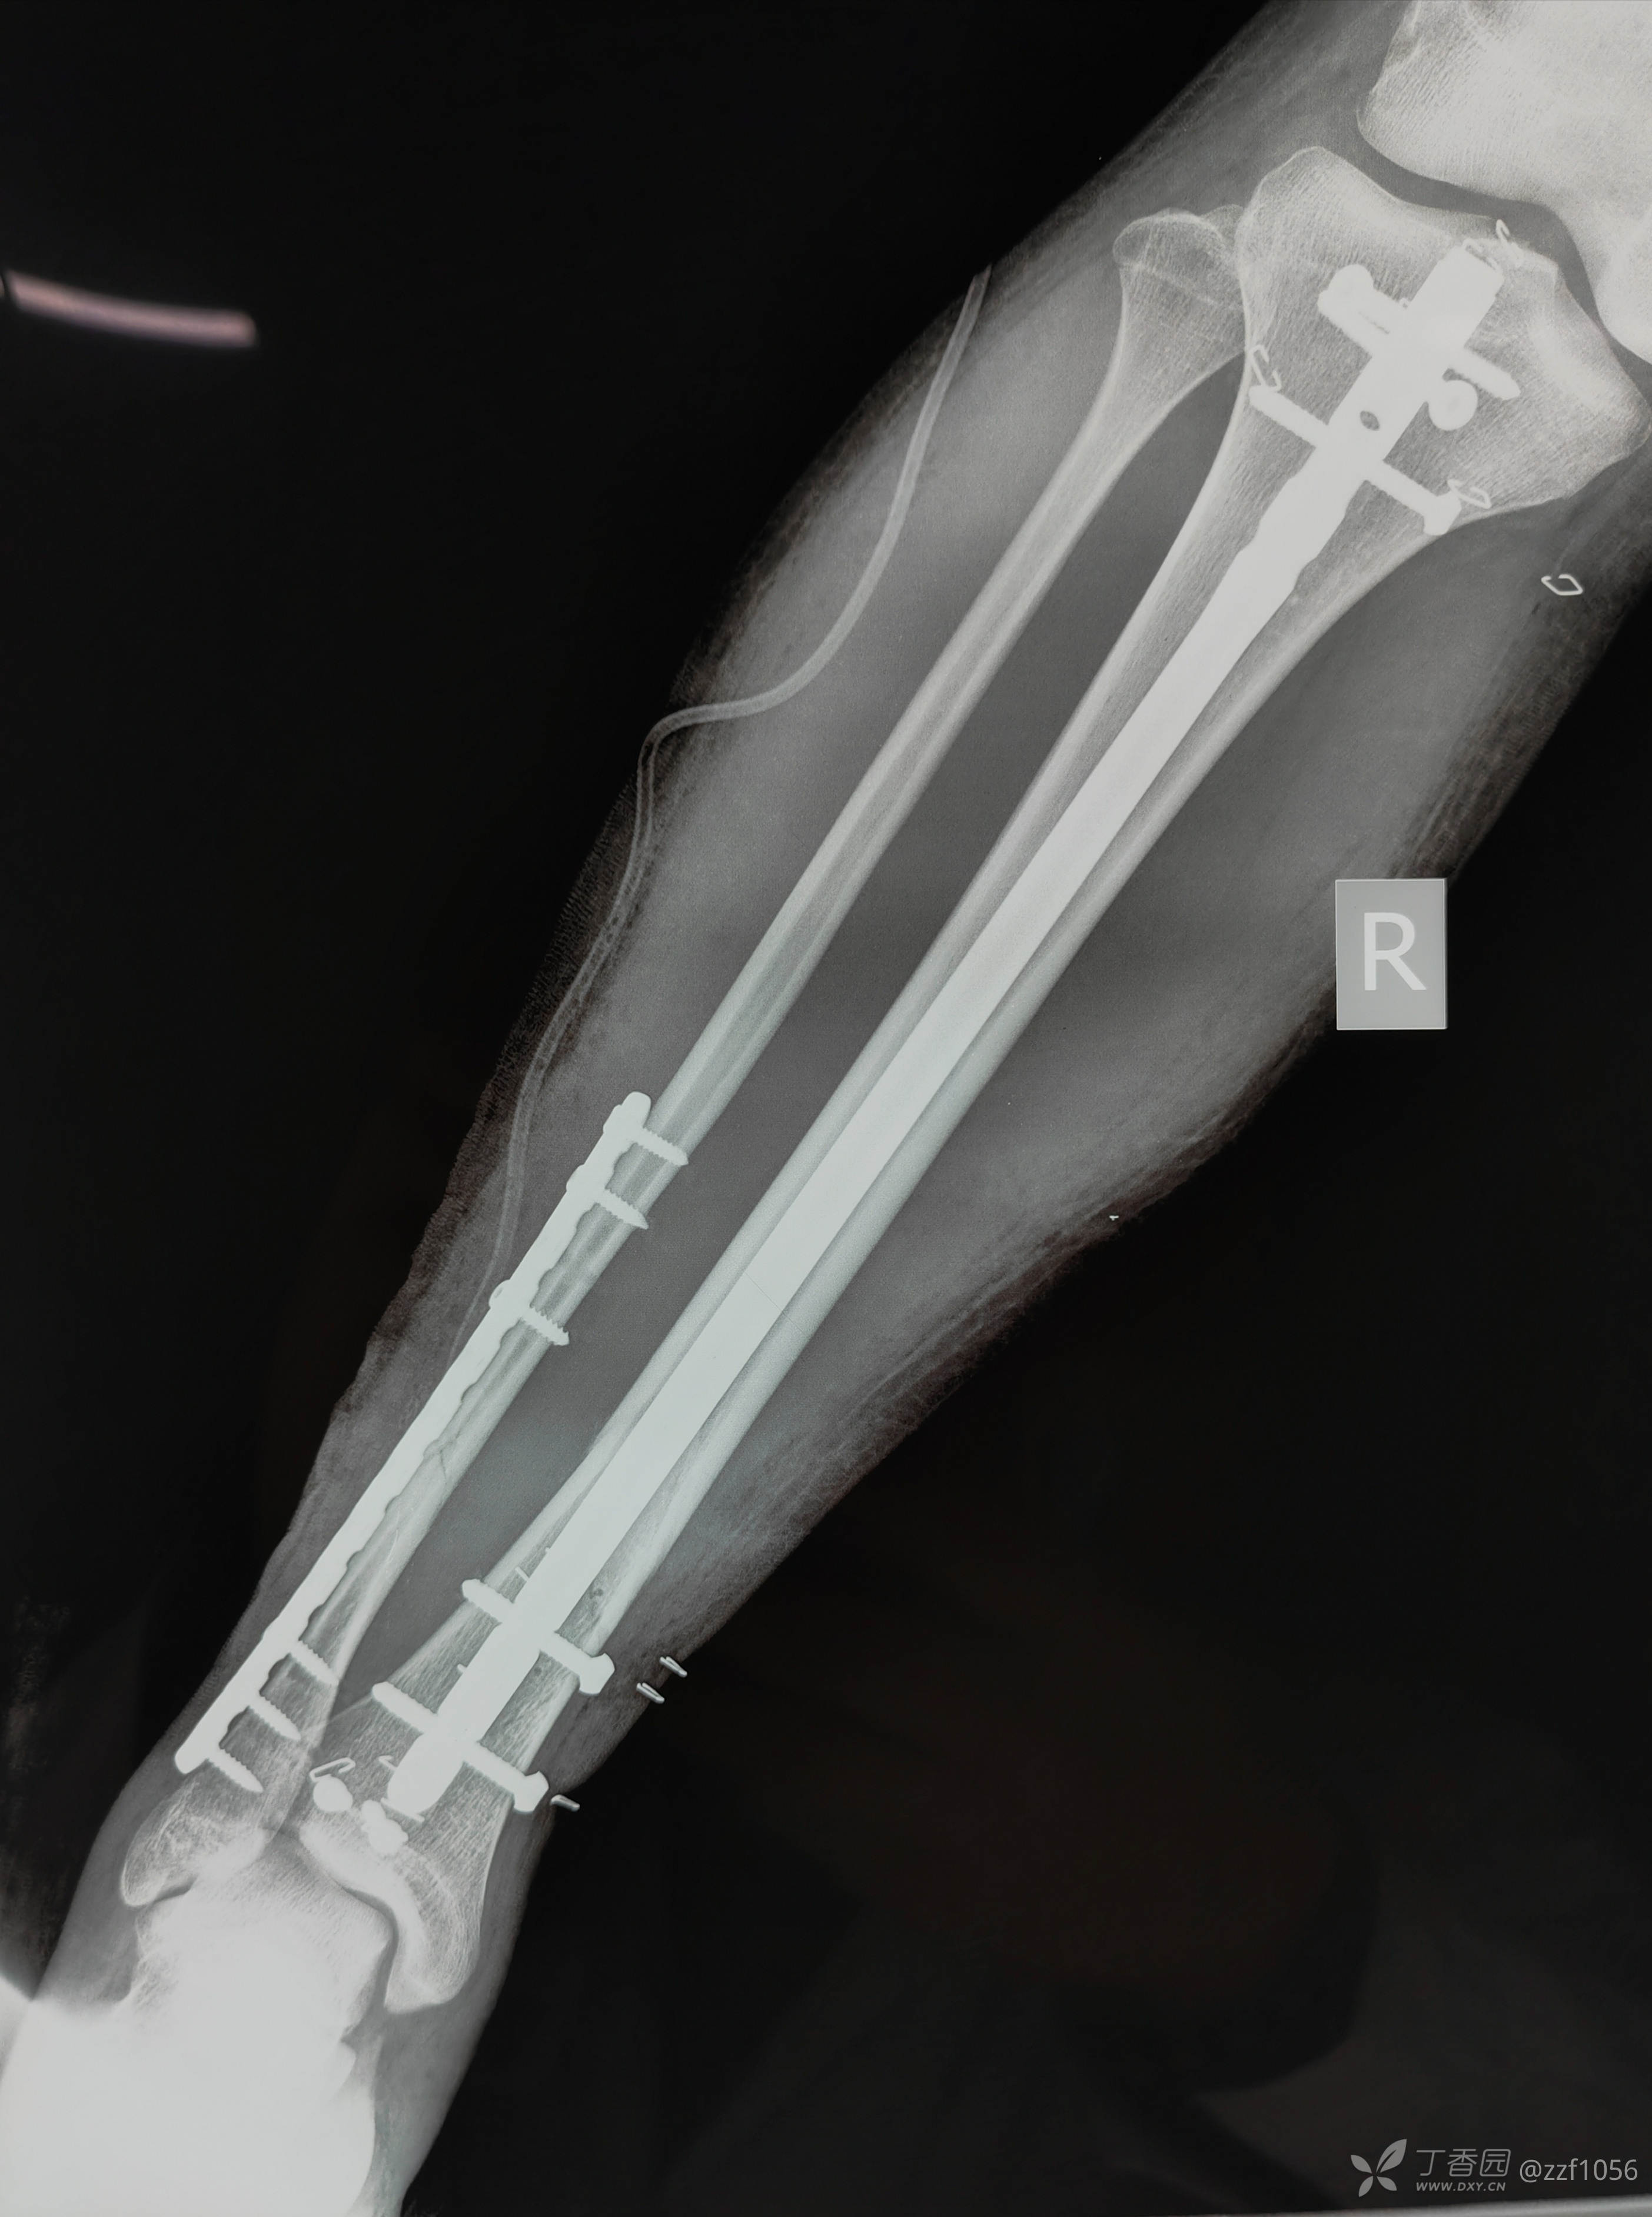

2022第一例~阻挡钉(Poller钉)技术辅助髓内钉再次治疗胫腓骨张—侯氏骨折

王某,男,19岁,因“被彩钢板砸伤致右小腿肿痛畸形10小时。”

入院诊断:右侧胫腓骨粉碎性骨折

入院3天后手术治疗

克氏针临时固定后踝,阻挡钉技术辅助髓内钉复位纠正成角畸形,您一般用多大的克氏针呢?

术后效果显著